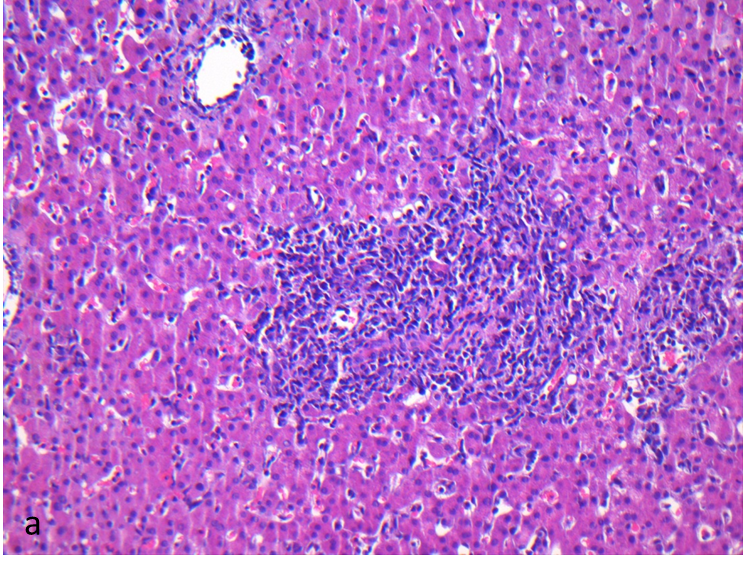

Falls nach einer Organtransplantation Komplikationen auftreten, kann über eine Gewebsentnahme die Ursache feingeweblich bestimmt werden. Hier ist es wichtig, eine Organabstoßung von einer Infektion oder einem Ischämie-/Reperfusionsschaden zu unterscheiden.

- Histologie: Die Standardmethode einer pathologischen Befundung ist die Anfertigung eines Gewebeschnittes mittels Gefrierschnitttechnik oder Paraffin-Einbettung. Anschließend werden unterschiedliche Färbungen angewendet um eine optimale Diagnostik sicherzustellen.